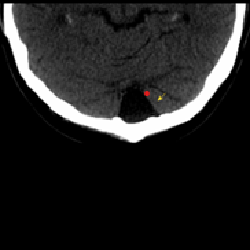

Por favor, inscríbete en curso antes de realizar este cuestionario. 1. Una de las maneras para diferenciar una asimetría ventricular y una hidrocefalia es mirar ¿qué astas?1 Temporales Occipitales Frontales 2. ¿A qué corresponde esta imagen?1 Megascisterna magna Higroma Espacio subracnoideo Quiste aracnoideo 3. La plagiocefalia postural se puede confundir con una craneosinostosis por sutura temprana de1 Coronal Lamboidea Metópica 4. ¿Qué variante anatómica vemos en la imagen?1 Quiste aracnoideo Cavum pellucidum Cavum interpositum Cavum vergae ¿Cómo interpretar una tomografía? Módulo 2 - Anatomía Volver a: Errores radiológicos